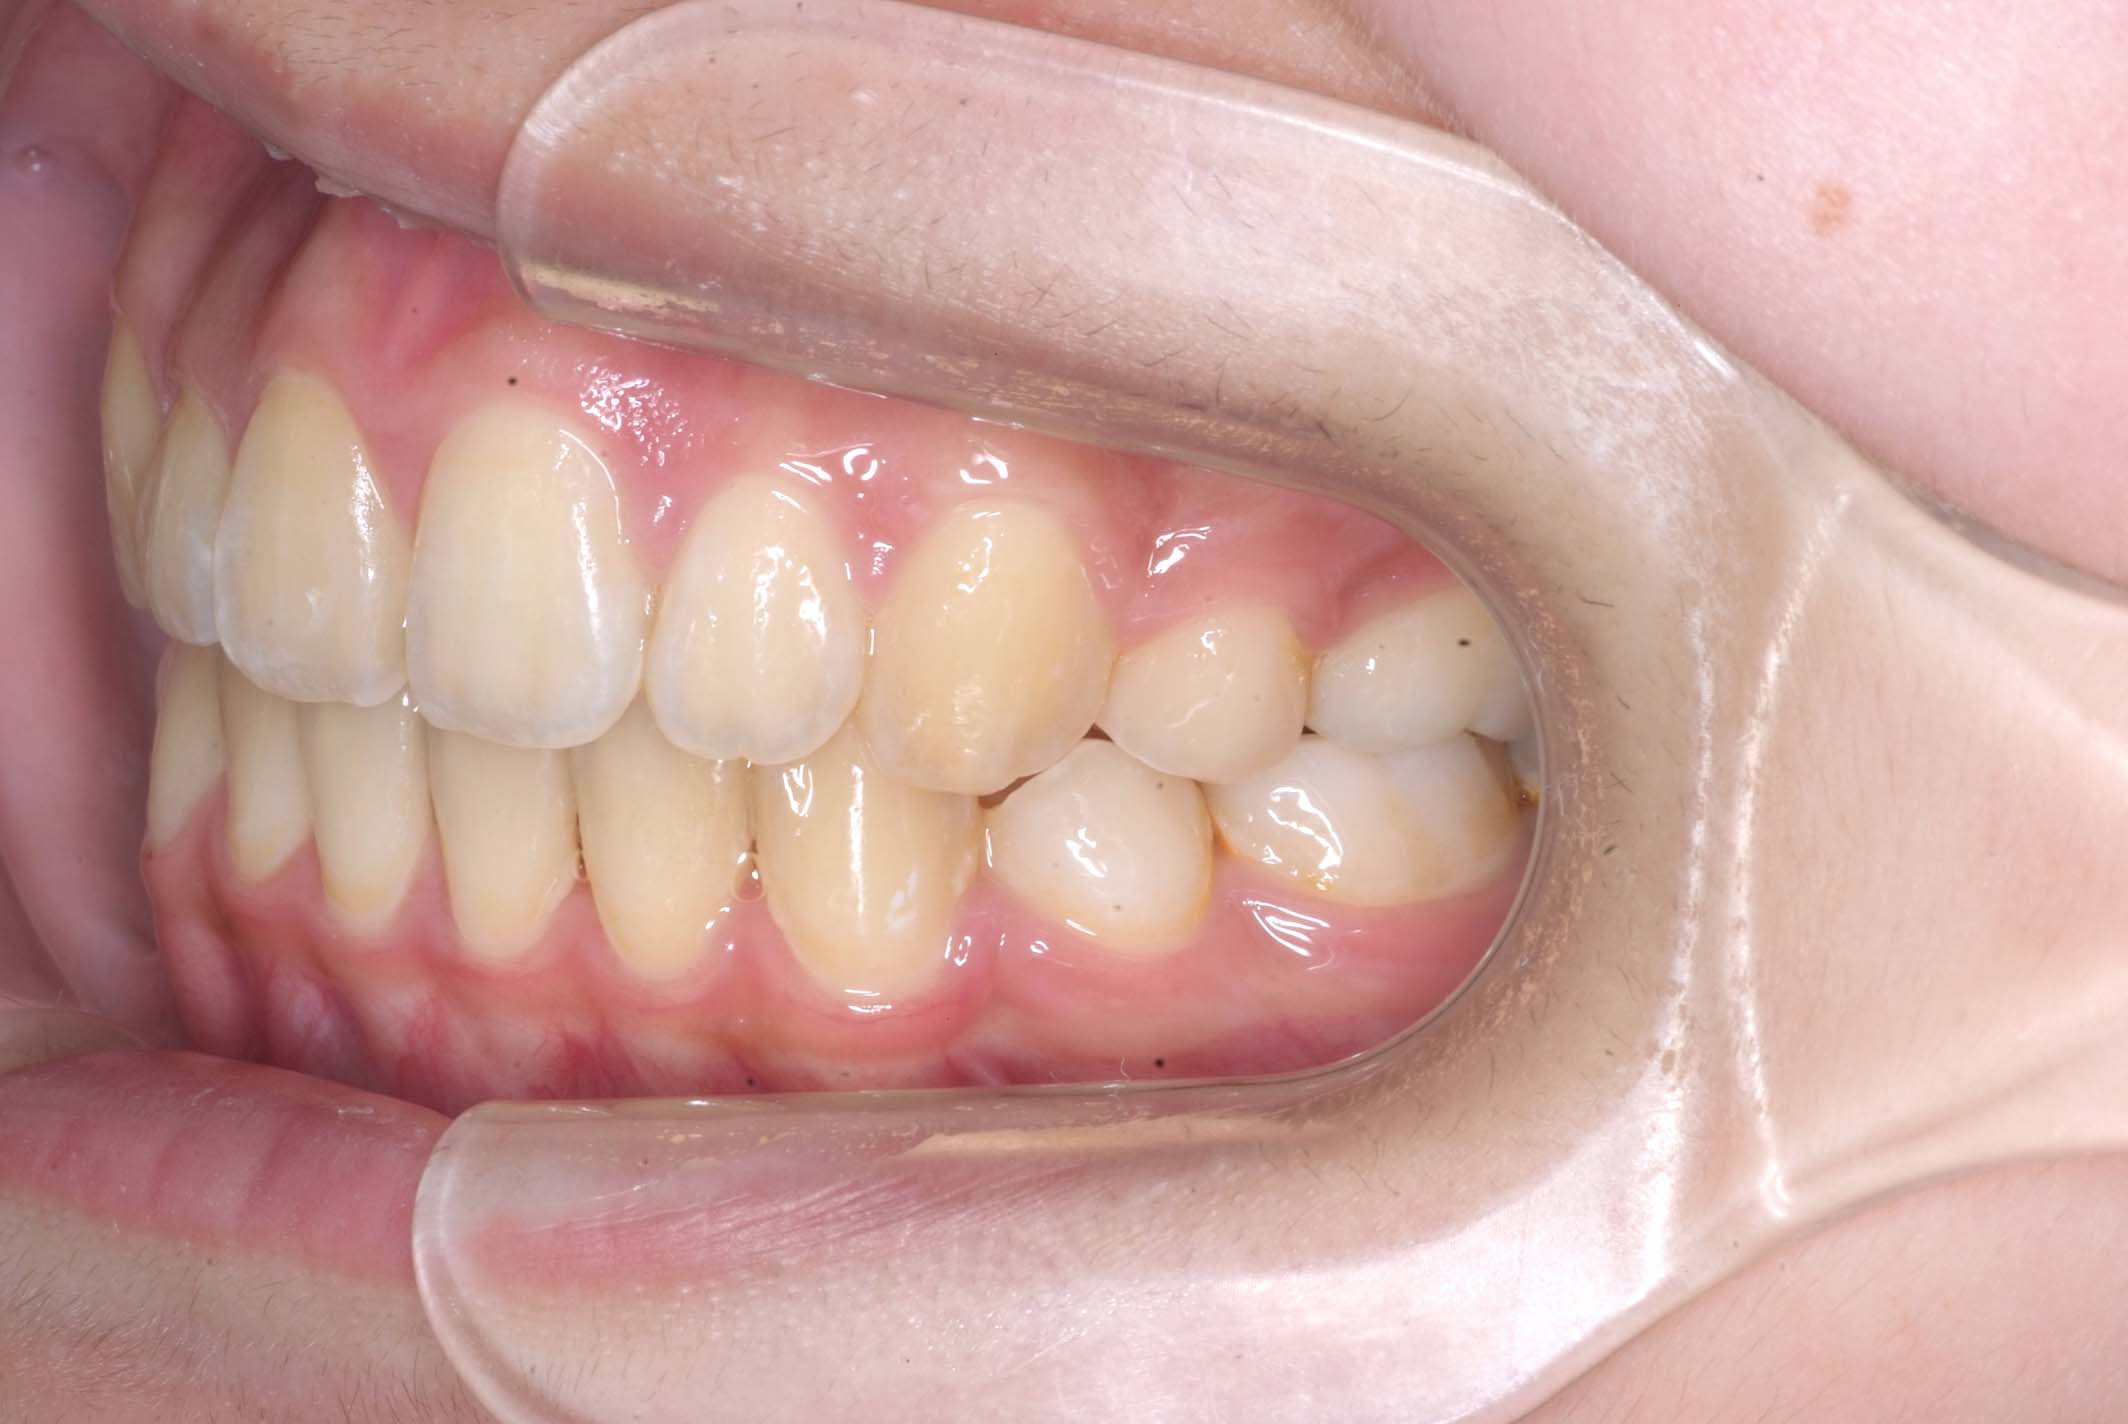

初診時年齢8才の女子で、前歯部開咬を気にして来院されました。

検査の結果、前歯部開咬と正中離開と上下顎前歯唇側傾斜を伴うアングルⅡ級1類不正咬合と診断しました。

前期治療は、リンガルアーチで正中離開を改善し、その後は歯列矯正用咬合誘導装置(マイオブレース)を使用して舌のトレーニングを行いました。後期治療は、上下左右4番を抜歯の上、セルフライゲーションブラケット装置(クリアティ・ウルトラ)で行いました。治療期間は前後期合わせて6年6ヶ月でした。通院回数:60回。